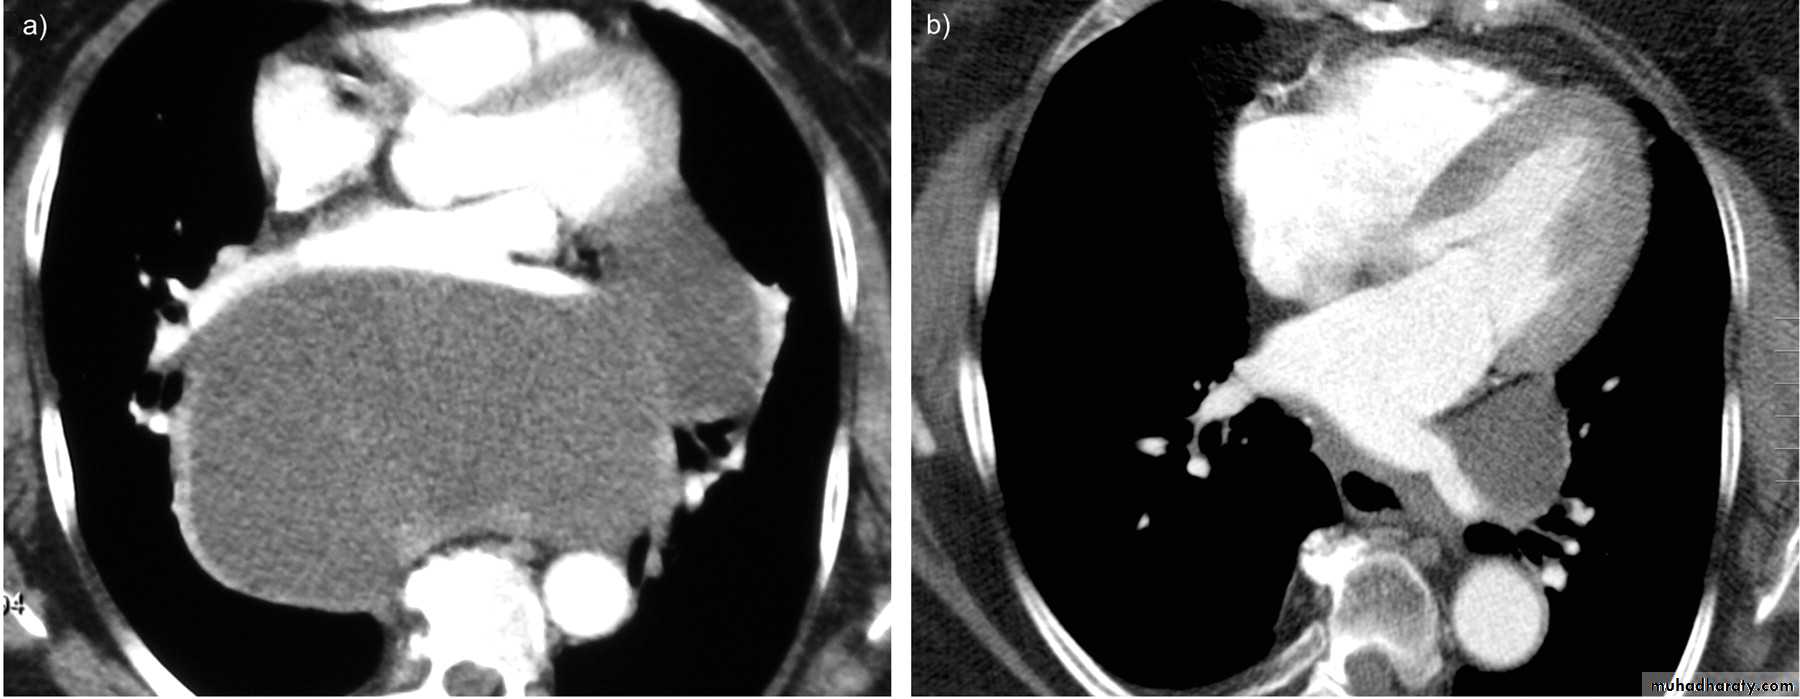

Empyema

EmpyemaX-ray Empyema

Pulmonary hydatid disease